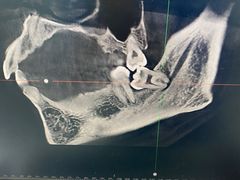

• 牙博士口腔品牌连锁(杨浦店)

• -牙博士口腔品牌连锁(杨浦店)

070103的 | 23-02-12